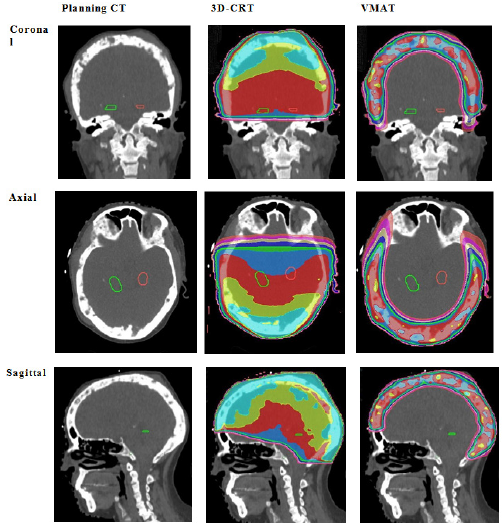

The dosimetry of 3DCRT compared to VMAT is displayed in Figure 1. Both gave a homogenous dose to the PTV but VMAT had superior conformity of dose to PTV. This is made evident when comparing the dosimetry in two perpendicular planes: inferior to superior and left to right. As seen in Figure 2, 3D-CRT uses large fields to ensure homogeneity to PTV but will inadvertently capture OARs in the concavity of the PTV within such fields. VMAT, on the other hand, achieves the same dose to PTV by irradiating through an arc. As there is dose from almost all directions, this allows for selective dose modulation to avoid OARs.

Figure 1 Comparative dosimetry of the 3DCRT and VMAT plans.

Figure 1A Comparison of baseline Planning CT, 3D-CRT planning volumes and VMAT planning volumes. Hippocampi contoured in green (left) and red (right). The first column shows the planning scan. Note the obvious metastases within the skull. The second column shows the 3D-CRT plan, the third column shows the VMAT plan. The top row shows coronal slices, second row shows the axial slices, and the third row shows the sagittal slices.  Note the exposure of healthy brain tissue to significant doses of radiation with 3D-CRT. Descriptive interpretation: this figure compares the dosimetry graphically between VMAT and 3D-CRT in three planes.

We present a case of a 54-year-old female with MM involving the skull, manifesting with refractory headaches, cranial neuropathy and tender skull masses. Despite the palliative nature of the treatment intent, her potential longevity was kept in mind and radiation induced brain injury (RIBI) was avoided by minimising the amount of healthy brain tissue in the treated volume, especially the hippocampi, as seen in Figure 3. The case shows excellent conformity of dose to PTV with VMAT in two perpendicular planes of convexity: inferior to superior and left to right a seen in Figure 1, clearly demonstrating that VMAT dosimetry was superior to 3DCRT for OAR avoidance.